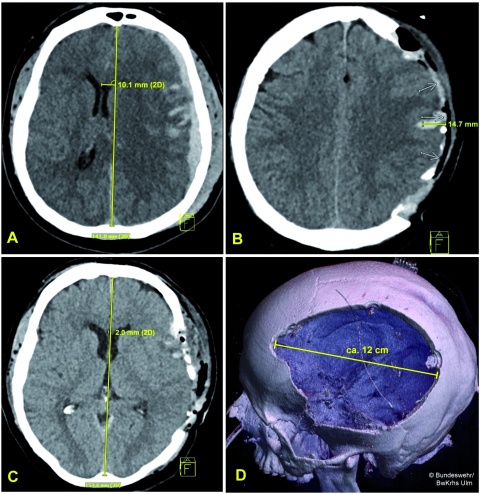

Schädel-Hirn-Trauma